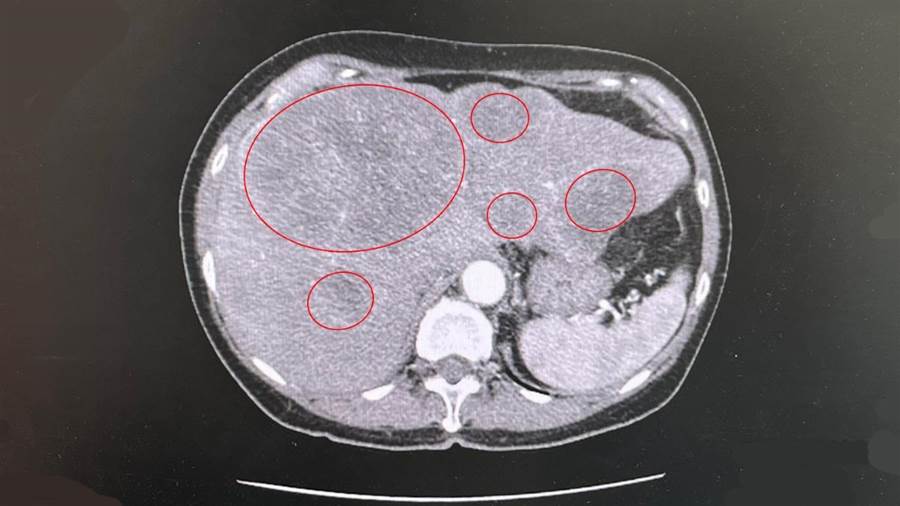

媽祖也指示她到澄清醫院中港院區找大腸直腸外科醫師陳周誠,經診斷女信徒確診直腸癌,並已移轉肝臟,肝臟腫瘤超過10顆猶如滿天星,緊急動刀後搭配化療,最終女信徒順利撿回一命,正持續追蹤觀察中。

而陳周誠也透過大腸鏡檢查診斷,女信徒直腸上段三分之一處有一顆約7公分大的癌腫瘤,並轉移至肝臟,腹部電腦斷層掃描也看見肝臟佈滿大大小小,由1公分到6.

于是女信徒也進行直腸癌手術,切除一段約19公分的直腸,再接合前後段正常直腸,陳周誠說明,術後腫瘤RAS基因檢驗顯示為野生型,因此對女信徒的肝腫瘤進行抗表皮生長因子標靶藥物合併化學治療,每三週住院注射一次,現階段女信徒于十天後順利出院,持續觀察中。